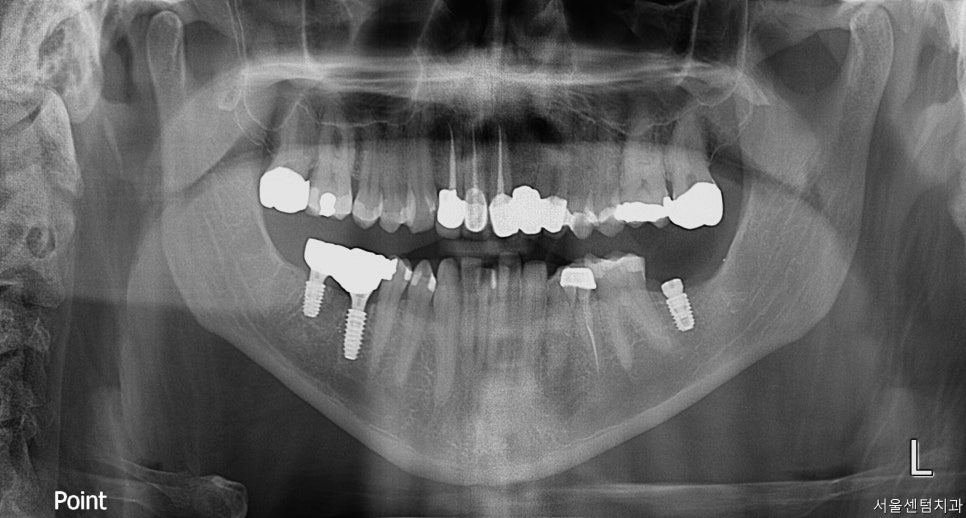

#37번은 발치가 이미 되어있었는데요.

여기는 생각보다 뼈가 더 없어서

뼈이식을 더 많이 하고 진행하게 되었습니다.

그래서 식립 후 힐링이 아닌 커버 스크류를 써서

좀 더 뼈랑 잘 유착이 되도록 만들었습니다.

여기는 좀 더 기다려야 할 것 같아

3개월 뒤 2차 OP 진행하기로 하였습니다.

한 달 뒤에 진행하게 된 2차 수술

씨티로 촬영하여 경과를 파악한 결과 2차 수술을

다음번에 해야 하는 상황으로 진단이 되었습니다.

씨티 체크 후에 다음 방문에 2차 OP를

진행하기로 결정했습니다.